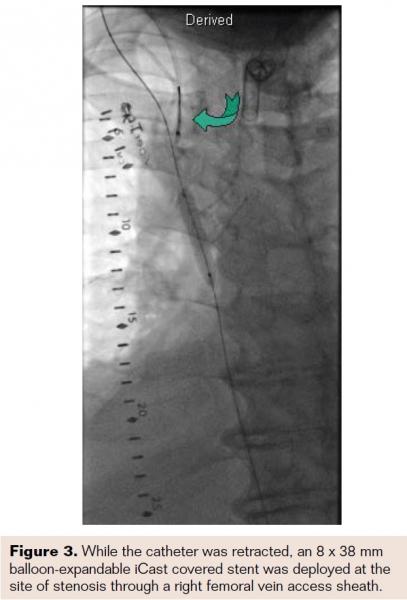

The right femoral vein was punctured and a 7 Fr introducer sheath was placed. Diagnostic venography was performed with a pigtail catheter, which revealed a severe stenosis of the SVC (Figure 1). Subsequently, a 6 Fr sheath was inserted in the right jugular vein using ultrasound guidance. The area of stenosis was crossed with a 0.014˝ Asahi Prowater wire (Abbott Vascular) via the right jugular vein. The patient was heparinized for an activated clotting time >250 sec. Intravascular ultrasound (Volcano, Eagle Eye platinum 3.5 x 150) was performed and demonstrated severe stenosis with reference vessel diameter of 8.0 mm (Figures 2A and 2B). The port-a-cath was located in the area of potential stenting. We used a 4-8 mm EnSnare (Merit Medical, Inc) from the right internal jugular vein to snare and then retract the tip of the port-a-cath cephalad. While the catheter was retracted, an 8 x 38 mm balloon-expandable iCAST covered stent (Atrium) was deployed at the site of stenosis through a right femoral vein access sheath (Figure 3). This stent was postdilated with a 10 x 40 mm Mustang balloon (Boston Scientific). Finally, the snared port-a-cath was repositioned within the lumen of the iCast stent in the SVC. Excellent angiographic results were obtained with no residual stenosis. There were no complications. The symptoms markedly improved within 24 hours and he was discharged on anticoagulation therapy. The patient died 3 months following the procedure.